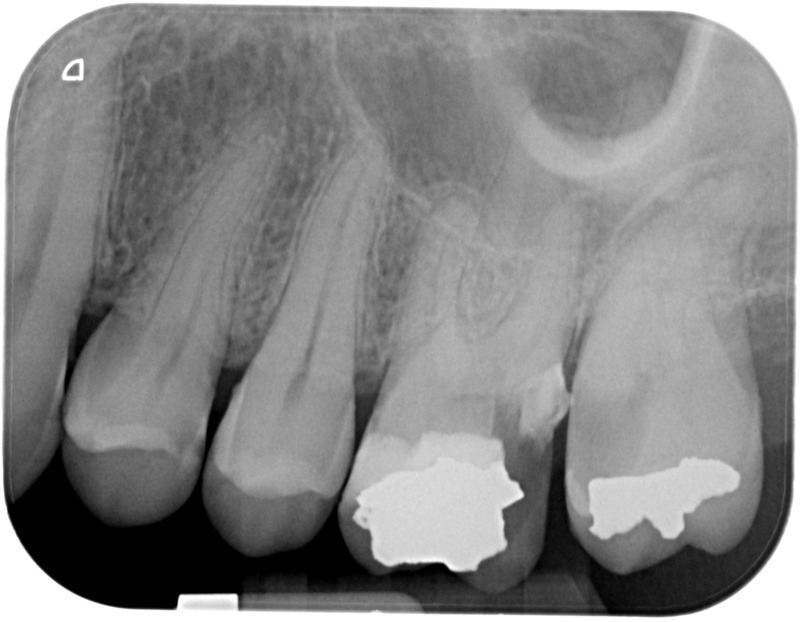

• Reprise de traitement endodontique : La manœuvre consiste à retourner à l’intérieur des racines d’une dent déjà traitée. Il arrive occasionnellement qu’une nouvelle inflammation se déclare suite à une reprise de carie ou une fracture de la dent, ou si le premier traitement endodontique est incomplet. Après s’être assuré que la dent lésée était conservable, il convient de désinfecter de nouveau le réseau canalaire parfois très complexe. La nouvelle obturation des canaux devra être protégée aussi rapidement que possible pour éviter une éventuelle contamination bactérienne.

Après